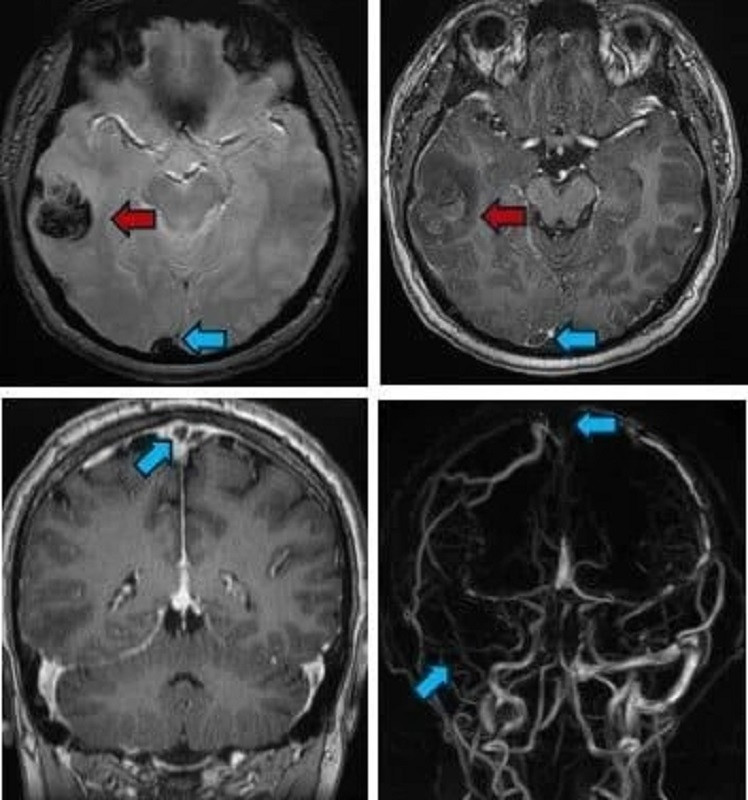

PGS.TS.BS Nguyễn Huy Thắng, Trưởng khoa Bệnh lý Mạch máu Não, Bệnh viện Nhân Dân 115 TPHCM cho biết, vừa tiếp nhận một thanh niên 22 tuổi (quê Cà Mau), nhập viện trong tình trạng đau đầu dữ dội. Kết quả chụp CT-scan cho thấy bệnh nhân bị xuất huyết não. Hình ảnh cộng hưởng từ phát hiện huyết khối tại nhiều vị trí trong hệ thống tĩnh mạch não của người bệnh.

| Bệnh nhân bị xuất huyết não vùng thái dương phải (mũi tên đỏ); huyết khối xoang tĩnh mạch dọc trên, xoang ngang – xoang sigma, tĩnh mạch vỏ não đính 2 bên (mũi tên xanh) |